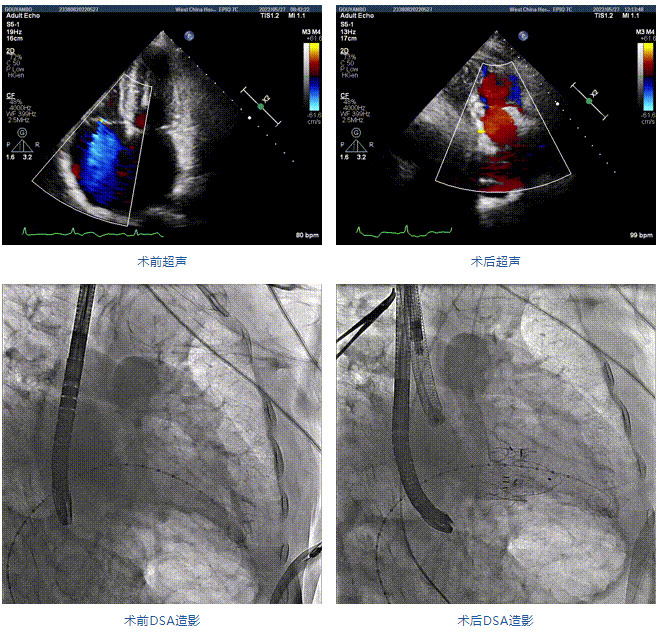

89歲男性。術(shù)前超聲報(bào)告顯示:雙房增大,左室壁肥厚,主、肺動(dòng)脈增寬,三尖瓣重度反流。

團(tuán)隊(duì)前期經(jīng)過多次討論,制定了周密的手術(shù)策略和預(yù)案。由于患者已是近九旬的超高齡老人,傳統(tǒng)外科開胸手術(shù)風(fēng)險(xiǎn)極高,純介入經(jīng)血管三尖瓣替換能夠明顯減少創(chuàng)傷。術(shù)中陳茂及馮沅教授結(jié)合體表定位在造影指示下精準(zhǔn)穿刺右側(cè)頸靜脈并預(yù)置兩把血管縫合器。成功建立經(jīng)皮血管入路后在食道超聲和DSA的引導(dǎo)下順利完成人工瓣膜植入,術(shù)后超聲和造影顯示人工三尖瓣同軸性良好,瓣架固定牢靠,無反流和瓣周漏,平均跨瓣壓差降為1mmHg。術(shù)畢收緊預(yù)置的血管縫合器縫線完成止血,縫合效果滿意,在手術(shù)室即刻拔除氣管插管。